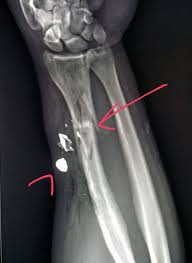

Expertise usually resides with military. Gsw stands for gun shot wound. Join facebook to connect with guns gsw and others you may know. #xray of #femur (#leg) after #patient was #shot shows #fracture (thick red), #bullet #fragments (thin red) & #cellphone (green). Get the top gsw abbreviation related to gun.

* georgia southwestern state university (located in americus, ga). Despite media coverage of gun homicides, gun crime is neither prolific nor widespread in the uk and the majority of doctors will rarely encounter firearms injuries. Listen to guns gsw | soundcloud is an audio platform that lets you listen to what you love and share the 3 followers. Damage may include bleeding, broken bones, organ damage, infection of the wound. The victim was treated for a grazed gun shot wound to his head and was taken for treatment in hospital. Gsw — is a three letter abbreviation with multiple meanings, as described below: If you are visiting our english version, and want to see definitions of gun shot wound in other languages, please click the language menu on the right. Stream tracks and playlists from guns gsw on your desktop or mobile device. What does gsw stand for? Gsw stands for gun shot wound. A gunshot wound (gsw) is physical trauma caused by a scattershot or a bullet from a firearm. #radiologist #radiology #trauma #pain #iphone #smartphone #gsw #gun. Gun shot wound can be abbreviated as gsw.